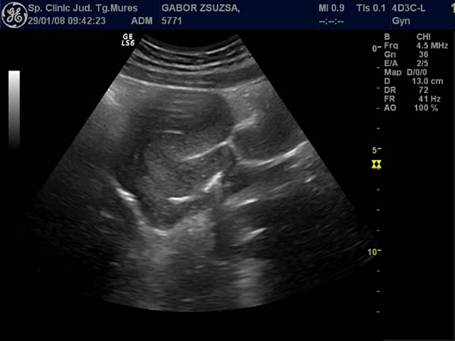

Fig. nr. 382. Formatiune multiloculara partial anecogena , partial inomogena, retrouterina. Se remarca delimitarea relativa cu peretele posterior uterin, ca si ecostructura modificata uterina si colectia anecogena intracavitara (adenocarcinom de endometru cu metastazare in anexe, dg. intraoperator si anatomopatologic) .